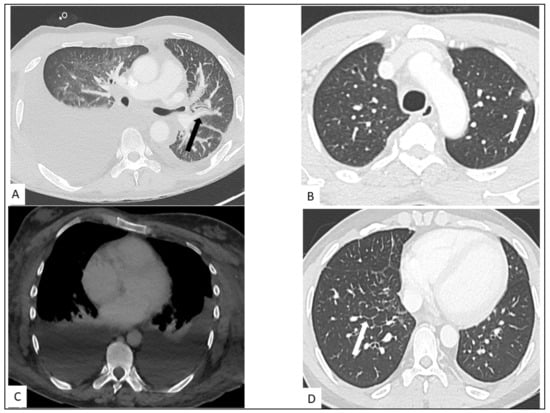

5.1. Pulmonary KS